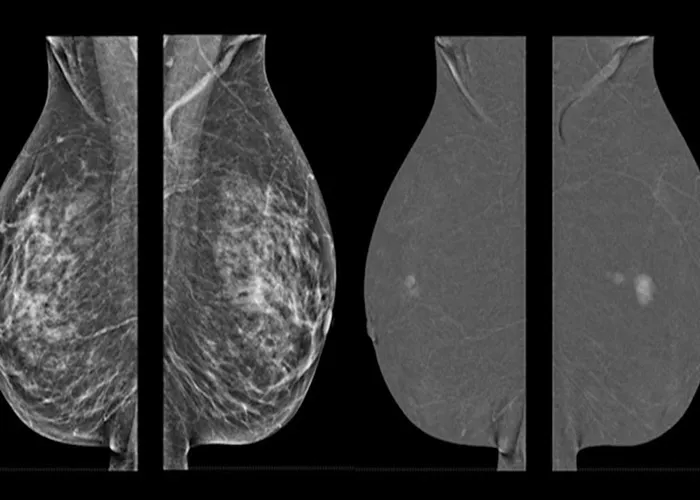

ماموگرافی دیجیتال یکی از پیشرفتهترین روشهای تصویربرداری پزشکی است که با استفاده از اشعه ایکس، از بافت سینه تصویری دقیق و باکیفیت ارائه میدهد. در این روش، تصاویر مستقیما بهصورت دیجیتال ثبت و ذخیره میشوند، بنابراین پزشکان میتوانند با بزرگنمایی یا بهبود وضوح تصویر، جزئیات بیشتری از ساختار بافت را بررسی کنند. این ویژگی دقت تشخیص را بهویژه در مراحل اولیه تغییرات یا تودههای مشکوک افزایش میدهد.

تفاوت اصلی ماموگرافی دیجیتال با نوع سنتی آن در نحوه پردازش دادهها است. در سیستمهای دیجیتال، نیاز به فیلمهای فیزیکی حذف شده و امکان تحلیل دقیقتر توسط نرمافزارها و الگوریتمهای هوش مصنوعی فراهم میشود. این تکنولوژی همچنین تابش اشعه کمتری دارد و برای خانمهایی که پروتز سینه دارند، ایمنی و دقت بیشتری نسبت به روشهای قدیمی فراهم میکند.

پروتز سینه در موقعیتهایی که در پشت بافت غدهای قرار میگیرد، میتواند بخشی از میدان دید اشعه ایکس را مسدود کند. این مانع باعث میشود برخی از نواحی بافت طبیعی سینه در تصاویر ماموگرافی بهدرستی دیده نشود. به همین دلیل، تکنسینهای باتجربه از روشهای خاصی برای تغییر زاویه تابش یا فشردهسازی استفاده میکنند تا نواحی پنهانشده نیز بهوضوح قابل مشاهده باشند.

یکی از تکنیکهای مرسوم، انجام چند تصویر اضافی از زوایای متفاوت است که به Eklund viewsمعروف است. در این روش، با جابهجایی دقیق پروتز و بافت سینه، تصاویر شفافتری بهدست میآید. این کار نیازمند مهارت و آگاهی کامل از ساختار ایمپلنت است تا هم از دقت تصویر اطمینان حاصل شود و هم هیچ آسیبی به پروتز وارد نگردد.

تحقیقات علمی طی سالهای اخیر نشان دادهاند که وجود پروتز سینه تاثیر مستقیمی بر توانایی تشخیص سرطان از طریق ماموگرافی دیجیتال ندارد، اما میتواند مشاهده بخشهایی از بافت را دشوارتر کند. مطالعات منتشرشده در مجلات تخصصی تصویربرداری سینه تاکید دارند که استفاده از تکنیکهای خاص مانند Eklund و انجام ماموگرافی توسط تکنسینهای باتجربه میتواند دقت تشخیص را به میزان قابلتوجهی افزایش دهد.

در مقابل، نتایج چند پژوهش بینالمللی بیان میکنند که ترکیب ماموگرافی دیجیتال با MRI یا سونوگرافی میتواند حساسیت تشخیص را تا ۹۰ درصد افزایش دهد. این موضوع بهویژه در خانمهایی که پروتز دارند، اهمیت دارد زیرا کمک میکند تا هرگونه تغییر در بافت یا شکل ایمپلنت بهموقع شناسایی شود و درمان در مراحل اولیه آغاز گردد.